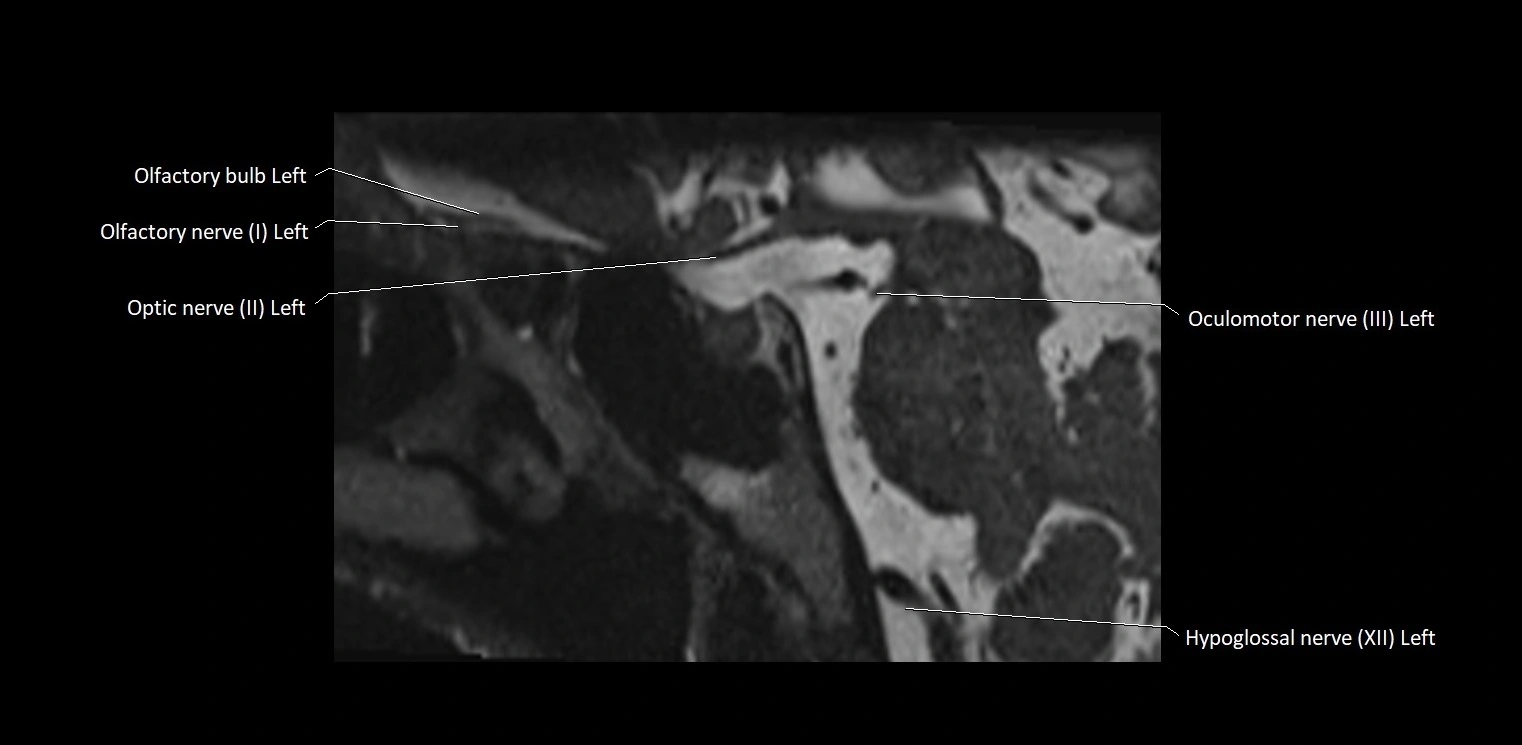

MRI images

image